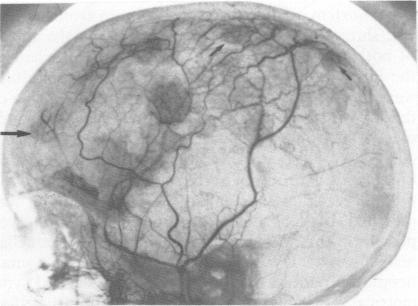

The clinical features of a family with inherited multiple meningiomas as the major manifestation of neurofibromatosis are presented. The value of noninvasive radiological screening investigations is emphasised. The results of cytogenetic and pathological studies on the family are presented and discussed with a review of the relevant literature.

本文报道了一个以遗传性多发性脑膜瘤为主要表现的神经纤维瘤病家族的临床特征。强调了无创性放射学筛查检查的价值。介绍并讨论了该家族的细胞遗传学和病理学研究结果,并对相关文献进行了综述。